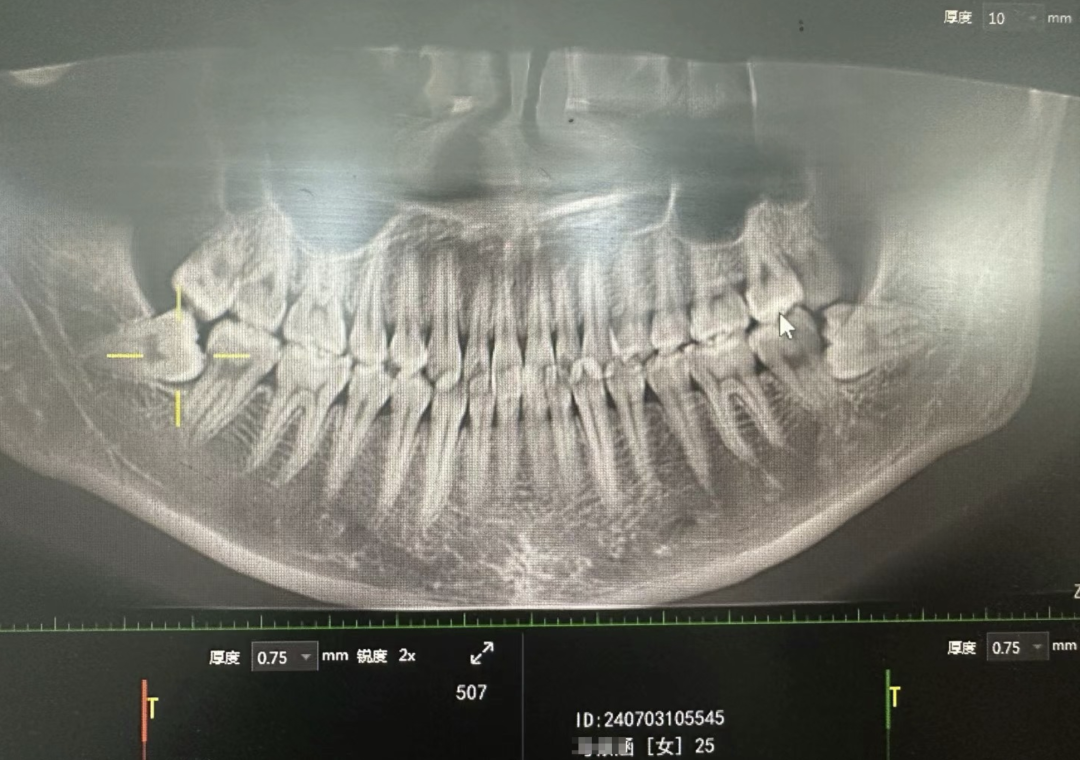

上图这种智齿很艰难的萌出,因为空间不足明显顶着第二恒磨牙长,这会引发第二恒磨牙的健康出现问题,并因为中间存在空隙导致容易堆积食物残渣难以清洁到位引发蛀牙问题等,甚至冠周炎都有一个专门的分类叫智齿冠周炎。

但不要觉得上图这种智齿是很严重的,相反那是最轻的,好歹都算萌出了,没办法萌出的智齿一大堆,甚至因为空间不足导致横着长的都有,生长目标十分明确的对准第二恒磨牙的牙根,不把宝贵的第二恒磨牙顶死誓不罢休。